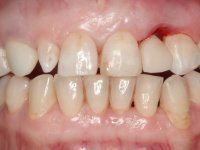

A paciente queixava-se que tinha um dente da frente a abanar, não gostava do “canino escuro” e também “queria fechar os espaços entre os dentes”. Passados 8 anos do tratamento inicial, o que motivou uma segunda fase de tratamento foi os “dois dentes da frente estarem feios”. Um ano após a última intervenção, apareceu um terceiro motivo para a terceira fase de tratamento, que foi a fratura da faceta feldspática colocada no dente 2.1.

O tratamento iniciou-se com a re -preparação do coto do espigão falso coto fundido, com o objetivo de colocar as linhas de acabamento cervical com uma localização intra-sulcular e simultaneamente confecionar uma coroa provisória adaptada. Com um tratamento ortodôntico muito simples, fechou-se o diastema entre os incisivos centrais superiores e estabilizou-se esta posição com um arame colocado na superfície palatina dos centrais, funcionando como contenção. Posteriormente procurou-se fazer uma tração ortodôntica lenta do dente 2.2 com o intuito de diminuir, ainda que muito ligeiramente a perda óssea vertical nessa zona. Finalizada a tração, foi feita a extração do dente 2.2 e a zona foi reabilitada provisoriamente com uma coroa de resina composta colada aos dentes adjacentes. Foi colocado um implante dentário na zona do dente 2.2 sendo novamente colada a coroa provisória em resina, reabilitando provisoriamente a paciente durante o período de osseointegração. No dente 1.3 foi feita uma gengivectomia com bisturi elétrico, com a intenção de subir o nível cervical do 1.3 conseguindo uma maior harmonia com o dente 2.3. Estabilizados os tecidos moles, foi feita uma impressão com a técnica de moldeira aberta, utilizando silicones de adição de consistência “putty” e “light”. A recolha da cor, tanto da componente dentária como dos tecidos moles foi feita pelo ceramista no consultório.  No laboratório as impressões foram passadas a gesso e deram origem a modelos de trabalho que foram devidamente analisados. Foi decidido confecionar um “abutment” metalo-cerâmico aparafusado sobre o implante. Este “abutment” foi fundido com uma liga nobre e posteriormente revestido a cerâmica coronária e gengival. Dada a inclinação do implante o aparafusamento condicionou de forma inevitável a saída do orifício do parafuso pela superfície vestibular. No sentido de esconder esta situação, o desenho do “abutment” já foi idealizado com a intenção de acomodar na superfície vestibular a colagem de uma faceta feldspática. Este “abutment” foi provado em boca e foram feitos ajustes no componente cerâmico gengival. A sua adaptação aos tecidos moles foi feita tanto de forma subtrativa, com broca, como de forma aditiva, acrescentando resina composta de tonalidade gengival. Este acrescento de resina seria orientador do ceramista na colocação final da cerâmica de tonalidade gengival. A coroa que reabilitaria o dente 1.3 foi cimentada nesta consulta de prova com cimento de ionómero de vidro reforçado com resina composta. Finalizado o trabalho em laboratório da faceta sobre o 1.2 e o “abutment” e a faceta para o implante este foi colado em boca, após a colocação do isolamento absoluto. O trabalho satisfez plenamente a paciente. Durante oito anos a paciente foi seguida regularmente, mostrando-se agradada com o tratamento efetuado, no entanto começou a mostrar interesse em intervir esteticamente nos incisivos centrais superiores. Decidida a segunda fase da nossa intervenção, foi feita a preparação dentária dos dentes 1.1 e 2.1 para a colocação de duas facetas feldspáticas. Particular cuidado foi tido na preparação inter-proximal distal junto ao “abutment” do implante. Foi preciso avaliar muito pormenorizadamente o eixo de inserção da faceta em relação ao “abutment”. As facetas feldspáticas foram confecionadas em laboratório e posteriormente coladas em boca após a colocação de isolamento absoluto. Um ano após, iniciamos a nossa terceira fase de tratamento, após a faceta colada no dente 2.1 ter fraturado. A preparação dentária foi feita sobre a faceta colada, procurando estender mais para palatino o interface inter-proximal distal. O objetivo seria passar para mais palatino do ponto de contacto o interface faceta-dente. O preparo dentário do dente 1.2 também foi muito reduzido, limitando-se a criar um eixo de inserção. Após confecionadas a coroa total e a faceta em laboratório foram coladas em boca. Primeiro foi colada a coroa utilizando-se um isolamento relativo com teflon, posteriormente foi colada a faceta após a colocação do isolamento absoluto. Na coroa utilizei este tipo de isolamento para evitar a utilização de grampos. Seria difícil de aplicar pela forma e dimensão do dente e agressivo para os tecidos moles. Após a colagem foi avaliada a integração oclusal do trabalho.